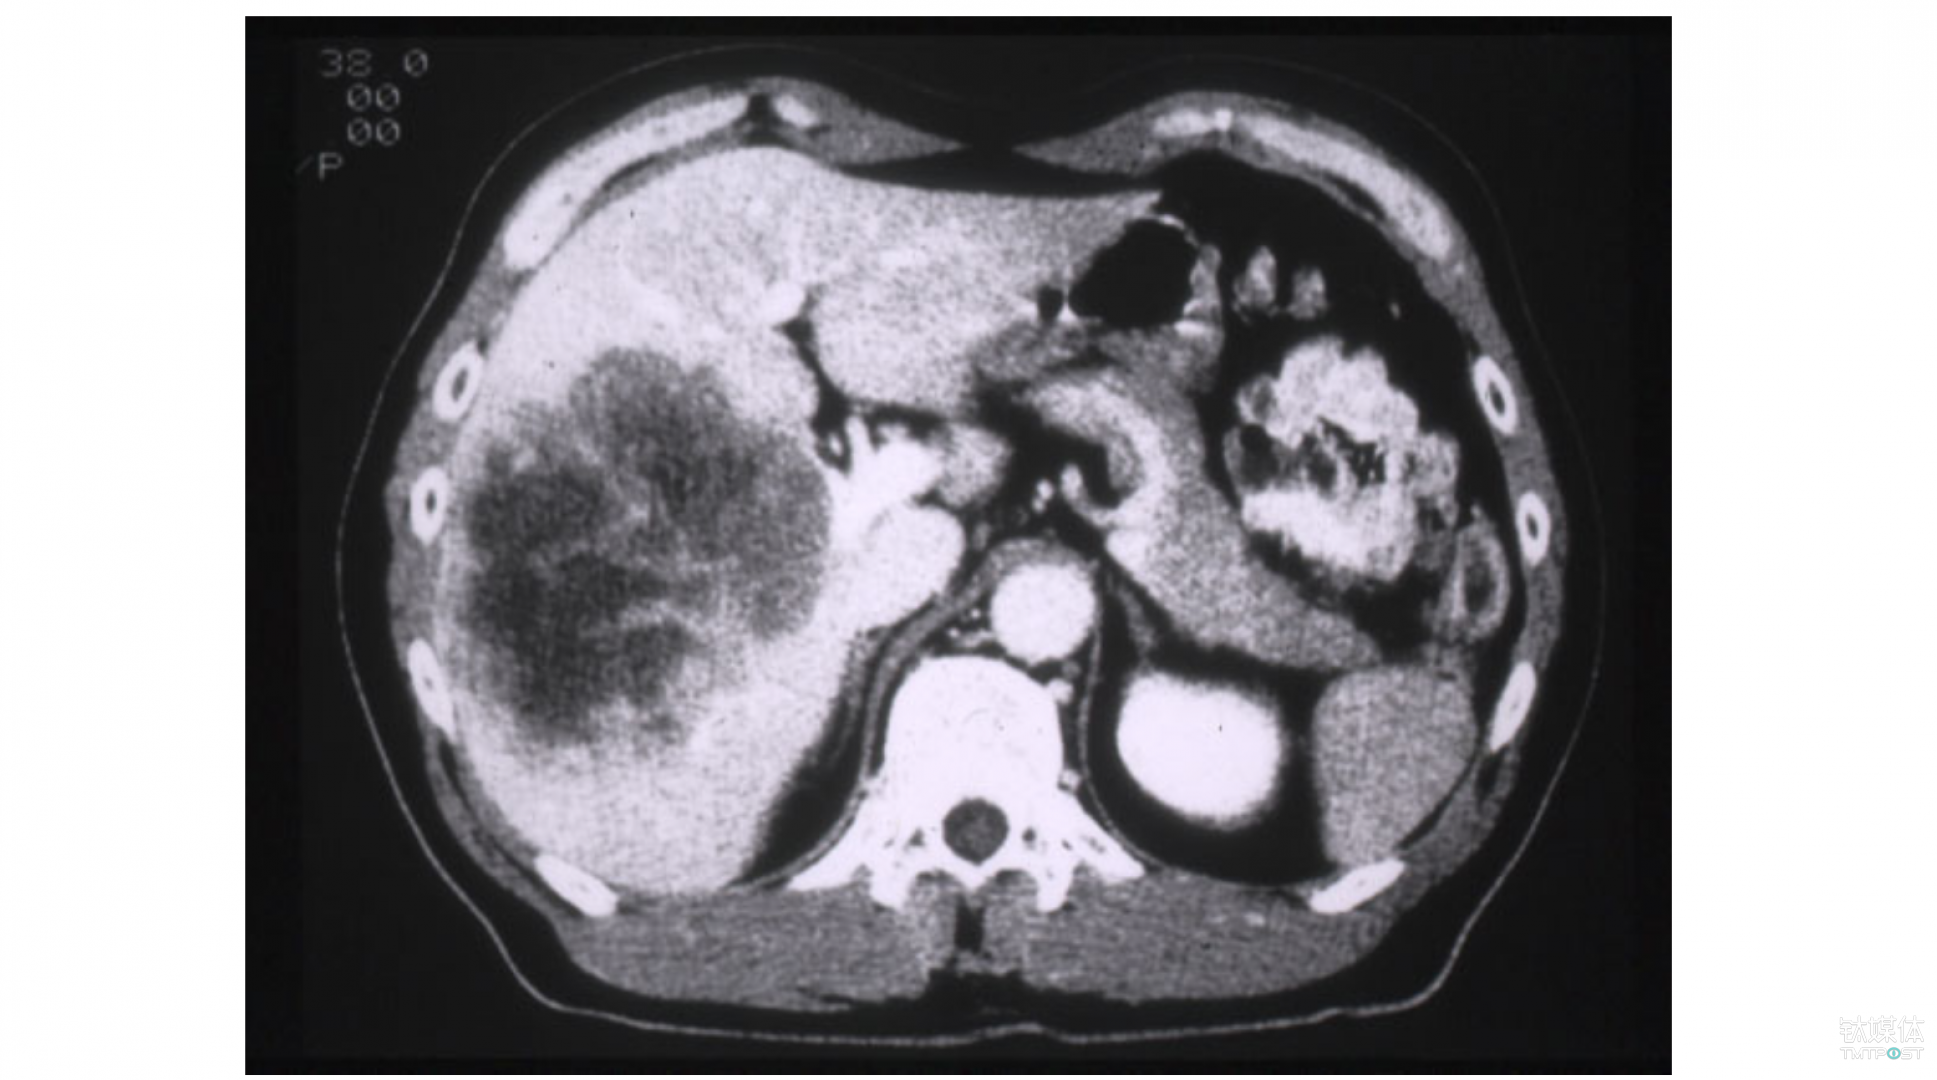

比如说这是对肝脏进行的一个CT图像,大家可以看到从腹部往上,这就是病人的肿瘤,这个肿瘤最终的处理方法是进行切除,但多数患有这种癌症的患者,其实他没有办法去接受切除术,因为他们国家的诊疗手段仍然是落后的。